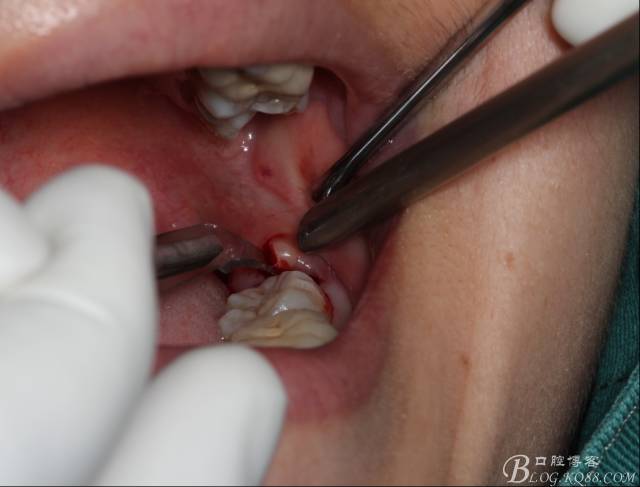

切開(kāi):角形切口,這個(gè)位置切開(kāi)我喜歡更易操作12#刀。

鈍性翻辨露冠

角度鍋輪機(jī)結(jié)合冷鹽水冷卻分冠

分冠完成

取出阻力部分冠

在取出阻力冠后,嘗試性看能取出全部的牙體不,就是取不出也能整體撬動(dòng)牙根。

計(jì)劃總趕不上變化,何況是充滿變異的智齒。由于可操作空間較小,原來(lái)計(jì)劃?rùn)M向分根改成矢狀分根。

現(xiàn)在都在提倡微創(chuàng),個(gè)人看法微創(chuàng)是相對(duì),所當(dāng)然微創(chuàng)是我們的追求。完全撥出,縫合關(guān)閉創(chuàng)口,常規(guī)智齒撥除醫(yī)囑,不適隨診。